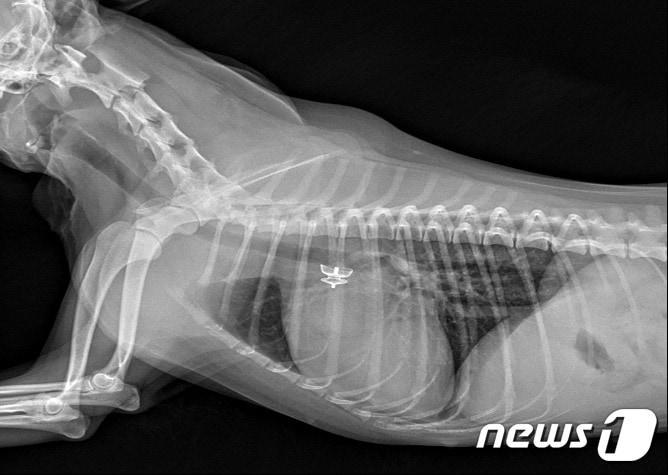

본문 이미지 - 선천성 심장병 동맥관 개존증(PDA) 앓는 강아지(VIP동물의료센터 제공) /뉴스1

선천성 심장병 동맥관 개존증(PDA) 앓는 강아지(VIP동물의료센터 제공) /뉴스1